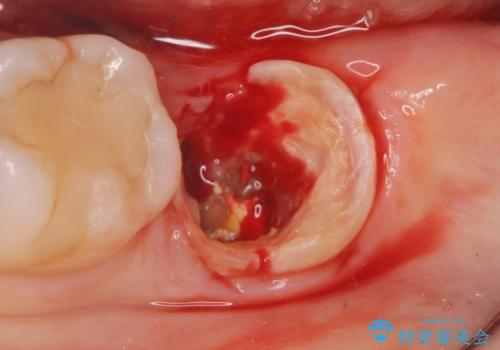

割れている奥歯を抜去後左上の機能していない親知らずを移植し、生着したのち根管治療・補綴を行いました。

- 外科手術のため、術後に痛みや腫れ、違和感を伴います

- 適応範囲に制限があります(健康な親知らず・移植歯が必要など)

- 移植歯が生着しない可能性があります

- 予後が不安定で歯によっては長く持たない可能性があります